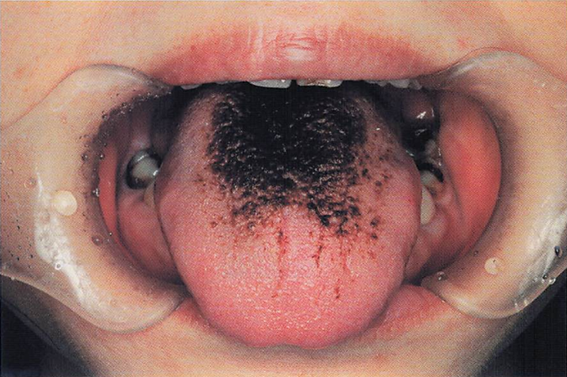

午前-52

54歳の女性。舌の異常を主訴として来院した。2週前に着色を自覚したが、疼痛がないため様子をみていたという。現在、気管支喘息、市中肺炎、 高血圧症および糖尿病に対して薬物療法を受けているという。初診時の口腔内写真 を別に示す。 原因と考えられるのはどれか。2つ選べ。

a.降圧薬

b.抗菌薬

c.血糖降下薬

d.副腎皮質ステロイド薬

解答を見る

b.d